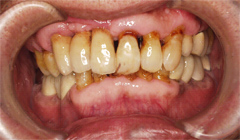

食事中に前歯がいきなりグラグラとしだした

食事中に前歯がぐらぐらしてきて、最初のころは、しばらく放っておいたそうですが、しばらくすると、前歯がついに折れてしまったということです。

患者様が吉本歯科医院に来院された時には、その他の歯もグラグラになっている部分があることが診断でわかりました。患者さまの自覚症状としては、「とにかく前歯をくっつけて欲しい」ということでした。

噛み合わせが非常に悪く、上の歯が下の歯にすっぽりと覆いかぶさっておりまともに噛めていない状態であることがわかりました。

・もともとの咬合不全(噛み合わせ(咬み合わせ)の悪さ)による前歯の破折

・歯を支える骨も溶けて薄くなってしまっている状態